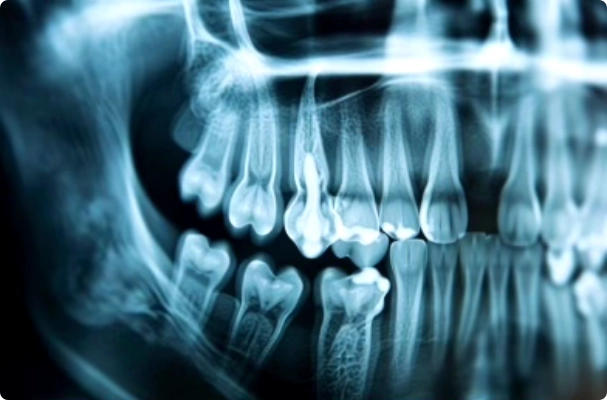

La première étape de la planification implantaire consiste en une évaluation complète de la santé bucco-dentaire du patient. Le dentiste examine les dents, les gencives et les os de la mâchoire à l’aide de radiographies et de scans 3D. Cette analyse permet de détecter toute condition qui pourrait affecter le placement de l’implant, telles que la résorption osseuse ou les maladies des gencives. Une évaluation approfondie est cruciale pour déterminer la viabilité de l’implantation et pour prévoir les éventuelles interventions nécessaires avant la pose des implants.

L’imagerie numérique, incluant la tomographie volumétrique à faisceau conique (CBCT), joue un rôle indispensable. Elle donne une vue détaillée de la structure osseuse de la mâchoire, ce qui permet de planifier précisément la zone d’insertion des implants. Ces images aident à éviter les structures critiques comme les nerfs et les sinus, réduisant ainsi le risque de complications. En utilisant ces technologies, les dentistes peuvent visualiser en trois dimensions l’anatomie de la mâchoire, facilitant ainsi une planification précise et détaillée.